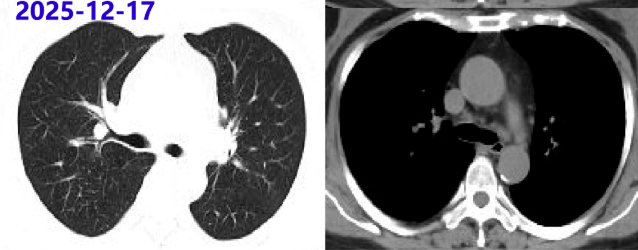

2025-01-22 胸部CT:较24-12-09片肺内病灶吸收,纵隔淋巴结缩小。激素减量方案:甲泼尼龙20mg qd×3周、16mg qd维持。

2025-04-16 胸部CT:较前片好转(最大淋巴结位于左下气管旁19×14mm);炎症指标、ACE阴性;目前甲泼尼龙16mg qd,后续减量方案:14mg qd×2月、12mg qd×2月。

2025-08-14 胸部CT:较前片相仿。后续减量方案:10mg qd×2月、8mg qd×2月。

2025-12-17 胸部CT:较前片相仿。继续甲泼尼龙8mg qd,2~3月后复查胸部CT。